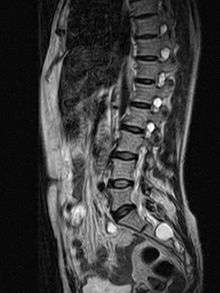

| MRI image showing a Tarlov cyst. | |

MRI, or Magnetic Resonance Imaging, is considered the imaging study of choice in identifying Tarlov cysts. MRI provides better resolution of tissue density, absence of bone interference, multiplanar capabilities, and is noninvasive. Plain films may show bony erosion of the spinal canal or of the sacral foramina On MRI pictures, the signal is the same as the CSF one.